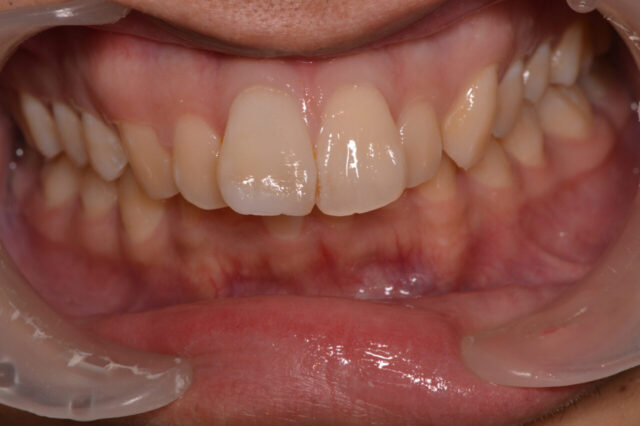

前歯の変色を削らずに改善|ホワイトニング+ダイレクトボンディング症例

性別 女性 主訴 「前歯の色が気になる」「できれば削らずにきれいにしたい」というご相談で来院されました。 治療 診査の結果、前歯には失活歯による内部からの変色(いわゆる黒ずみ)が認められました。

通常であれば、ラミネートベニアやセラミッククラウンによる修復が検討されるケースです。

しかし本症例では、歯質の保存を最優先に考え、以下の治療を選択しました。

インターナルブリーチ(ウォーキングブリーチ)による内部漂白

色調改善後にダイレクトボンディングによる形態・色調修正

まず歯の内部に漂白剤を作用させることで、歯質自体の明度を改善。

その後、周囲の歯との色調バランスを考慮しながらコンポジットレジンにて微調整を行いました。

結果として、歯を大きく削ることなく、自然で調和のとれた前歯の審美性を回復することができました。料金 1本10万円+tax 備考 本症例のポイントは、「削らない選択肢」を最大限活かした点にあります。

失活歯の変色に対しては、従来セラミック治療が第一選択とされることも多いですが、

インターナルブリーチを適切に行うことで、歯質を温存したまま審美改善が可能なケースも存在します。

また、ダイレクトボンディングを併用することで、

色調の微調整

透明感の再現

最小限の介入での形態修正

が可能となり、より自然な仕上がりが得られます。